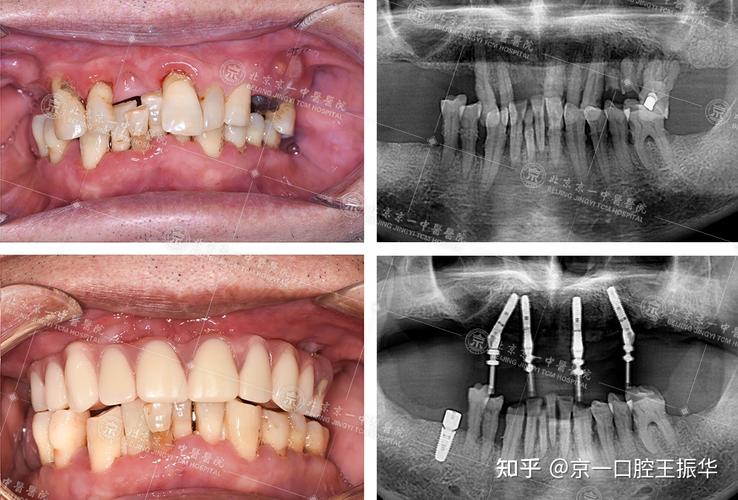

(图片来源网络,侵删)- 种植体品牌、基台类型(成品基台 vs. 个性化基台)、牙冠材料(全瓷、烤瓷)、是否需要植骨/上颌窦提升等附加手术,都会显著影响总费用。

(图片来源网络,侵删)- 信任专业判断: 医生会根据你的口腔状况和临床经验,推荐最适合你的品牌和型号,不要完全脱离医生建议盲目追求“顶级”或“最便宜”。